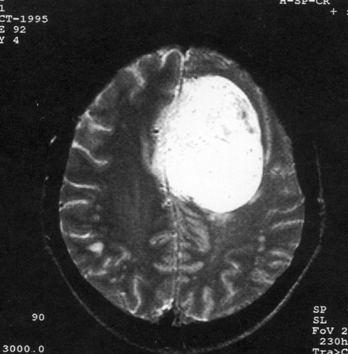

问题 病历摘要:??患者女性,37岁。大便时突起炸裂样头痛3小时,伴喷射样呕吐。既往体健。体检:T37.5℃,BP145/90mmHg,R20次/分,P85次/分。神志清楚,颅神经检查无异常,颈强直,克、布氏征(-),四肢肌力、肌张力正常,病理征(-)。 根据病史,最可能的诊断是什么?

选项 A.脑栓塞 B.脑血栓形成 C.蛛网膜下腔出血 D.脑炎 E.血管性头痛 F.脑膜炎 G.脑出血

答案 C